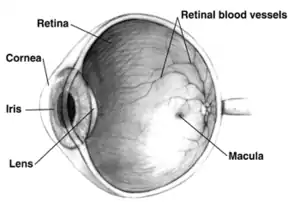

Far-sightedness, also known as hypermetropia, is a condition of the eye in which light is focused behind, instead of on, the retina.[2] This results in close objects appearing blurry, while far objects may appear normal.[2] As the condition worsens, objects at all distances may be blurry.[2] Other symptoms may include headaches and eye strain.[2] People may also experience accommodative dysfunction, binocular dysfunction, amblyopia, and strabismus.[3]

The cause is an imperfection of the eyes.[2] Often it occurs when the eyeball is too short, or the lens or cornea is misshapen.[2] Risk factors include a family history of the condition, diabetes, certain medications, and tumors around the eye.[2][4] It is a type of refractive error.[2] Diagnosis is based on an eye exam.[2]

- Axial: Axial hypermetropia occur when the axial length of eyeball is too short. About 1 mm decrease in axial length cause 3 diopters of hypermetropia.[6] One condition that cause axial hypermetropia is nanophthalmos.[7]

- Curvatural: Curvatural hypermetropia occur when curvature of lens or cornea is flatter than normal. About 1 mm increase in radius of curvature results in 6 diopters of hypermetropia.[6] Cornea is flatter in microcornea and cornea plana.[7]

Far-sightedness is often present from birth, but children have a very flexible eye lens, which helps to compensate.[9] In rare instances hyperopia can be due to diabetes, and problems with the blood vessels in the retina.[1]

A diagnosis of far-sightedness is made by utilizing either a retinoscope or an automated refractor-objective refraction; or trial lenses in a trial frame or a phoropter to obtain a subjective examination. Ancillary tests for abnormal structures and physiology can be made via a slit lamp test, which examines the cornea, conjunctiva, anterior chamber, and iris.[10][11]